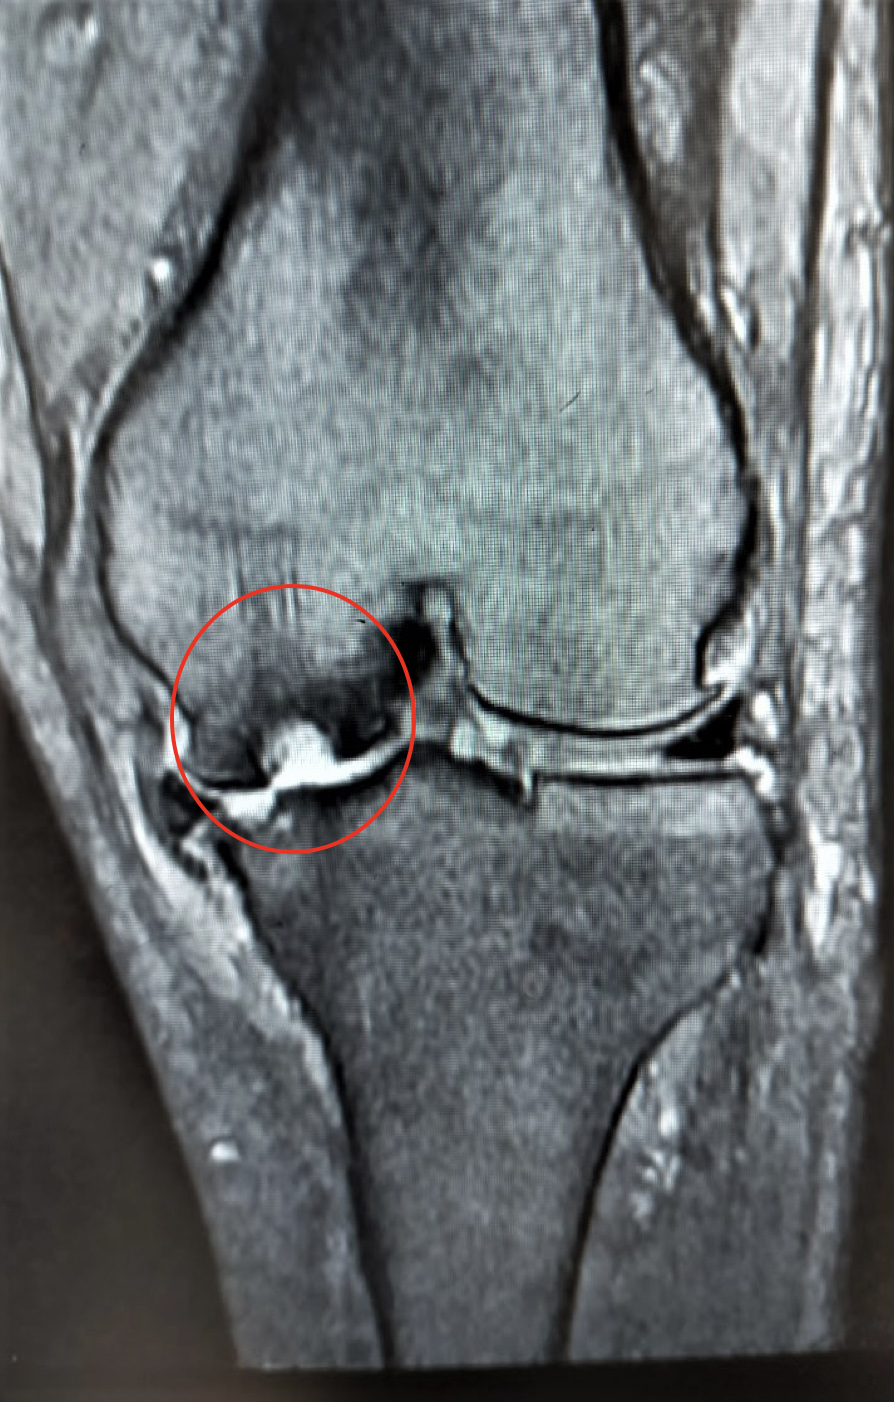

大腿骨顆部は体重を支えるのに重要で、過度なストレスが加わり壊死に陥ることがあります。

原因としてステロイド投与や半月板損傷後などに脆弱性骨折(軽微な外傷により軟骨下骨に微小骨折を生じる)が起こり壊死に至るとされています。安静にしていても痛みが出たり、夜間寝ている間に痛みが出ることもあります。

MRI